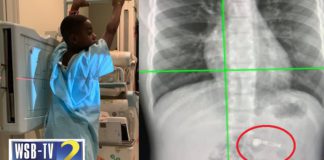

Hot Video

Video: Boy, 7, accidentally swallows AirPod Christmas gift